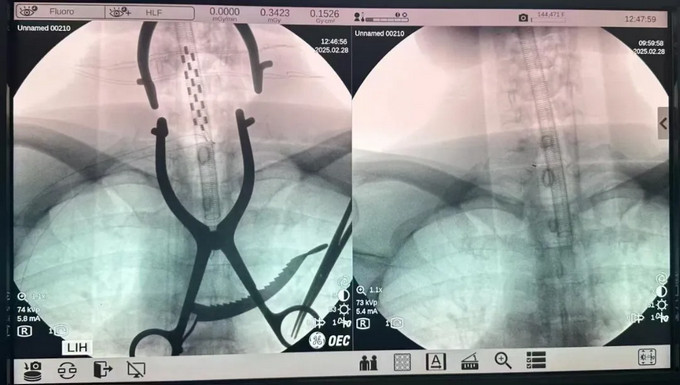

近日,黄播 神经外科成功开展了一台SCS(脊髓电刺激)手术,标志着黄播 在功能神经外科领域取得了重要突破。这一手术的成功实施,为偏瘫、肢体痉挛、昏迷促醒、顽固性疼痛、糖尿病足等患者带来了福音。

SCS手术作为功能神经外科的重要手术之一,主要用于治疗偏瘫、肢体痉挛、昏迷促醒、顽固性疼痛、糖尿病足等病症,通过精准的神经刺激,帮助患者改善肢体功能,提高生活质量。与此同时,针对外伤、脑出血、脑卒中后昏迷的患者,通过特定的神经调控技术,促进患者苏醒,让他们重获新生的希望。

此次SCS手术的顺利完成,不仅展示了黄播 神经外科团队精湛的医术和丰富的经验,更体现了医院在神经外科领域的先进技术水平,也为更多患者带来了康复的希望。